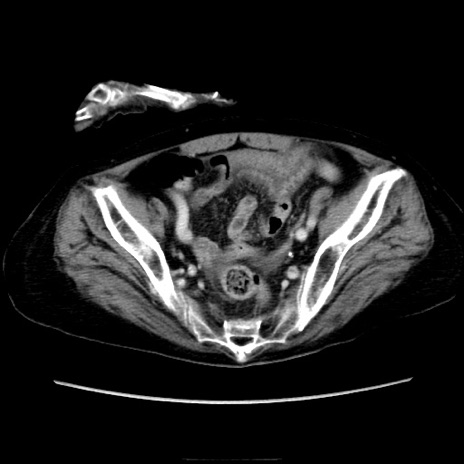

症例40(横断像)

【症例】90歳代女性

【主訴】腹痛・嘔吐

【現病歴】 食欲低下、嘔吐があり昨日他院受診。肺炎と診断され入院となる。入院後より腹部全体に圧痛あり。胃管留置され経過みていたが、症状持続するため、

当院転院となる。

【既往歴】胸椎圧迫骨折、胆石症

【身体所見】腹部:中央に激痛あり、圧痛あり、反跳痛不明

【データ】WBC 17100、CRP 18.82

横断像